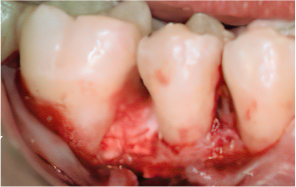

-

STEP 06

Flap closure and suturing